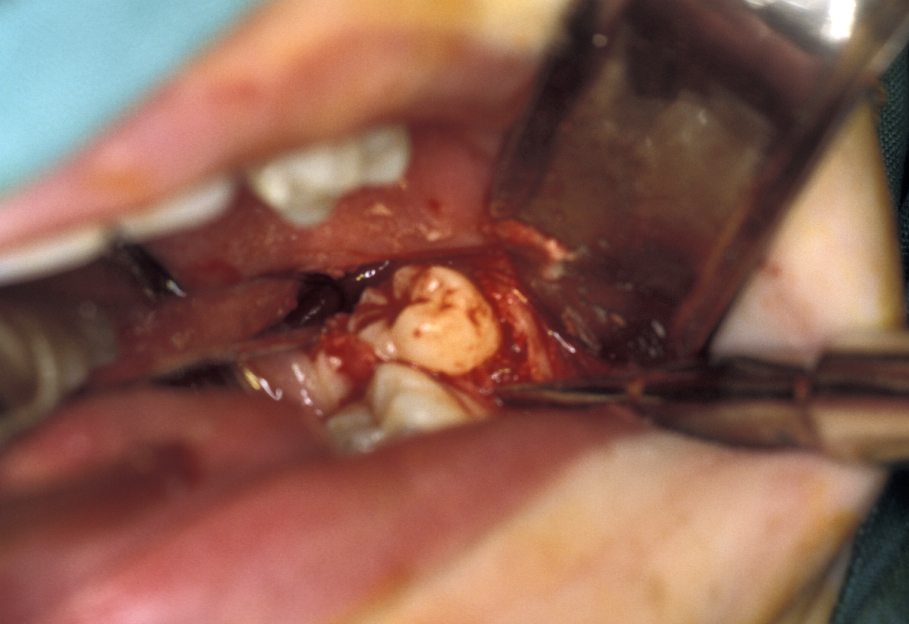

- Tooth removal – in less impacted cases a point of application may be drilled into the tooth, which is then elevated out of the socket (Figure 8). It is important not to lever the tooth out as any resistance may change the fulcrum of elevation and result in the inferior dental nerve being crushed. If the tooth does not elevate it may be better to divide it and remove it in pieces. This is where the unprotected lingual nerve may be damaged if the burr is passed too deeply.

The root pattern (Figure 11) and relationship to the inferior alveolar nerve bundle, to the adjacent second molar, and to bone of the ascending ramus of the mandible can all create problems with simple elevation of third molars. Sectioning the tooth is the safest technique to overcome this. The tooth is decoronated by cutting through the amelo-cemental junction (about 80% through), then the crown is fractured off with an elevator. If the tooth is still resistant to elevation, the roots are separated by cutting through the bifurcation and elevating them individually (Figure 12).